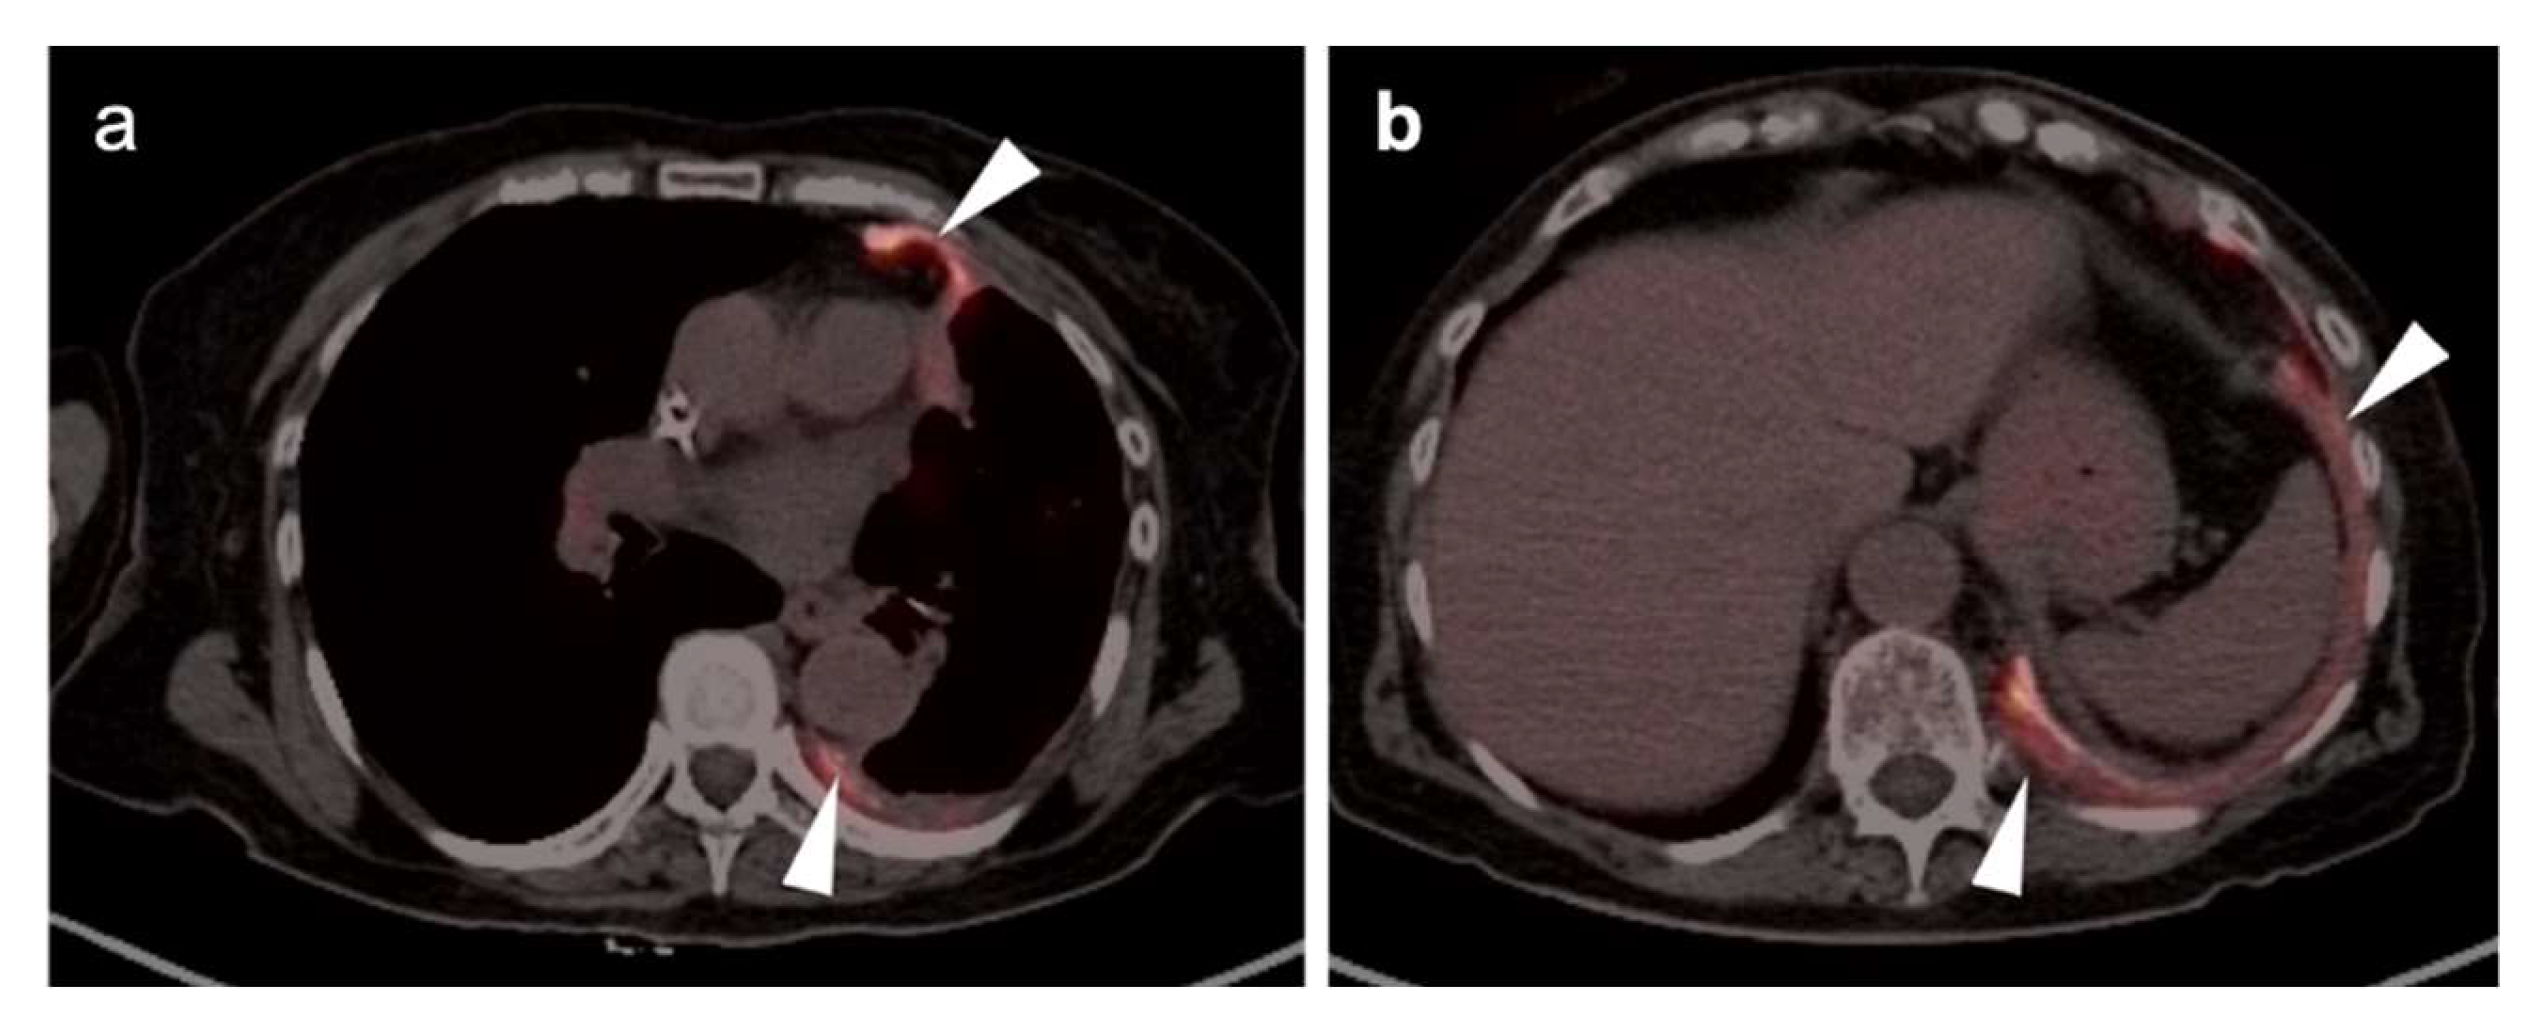

In diagnostic imaging of MPM, FDG PET-CT, whole-body MRI and PET-MRI show superiority over conventional CT [51]. MPM is typically intensely hypermetabolic on FDG PET-CT, making it highly amendable to staging by this method (Figure 13 and Figure 14). Hypermetabolic pleural thickening is typically associated with calcified pleural plaques but can be mimicked by hypermetabolic host inflammatory reaction to talc pleurodesis, empyema, and other pleural inflammatory disease, or by other subpleural malignant processes (Figure 15) [52]. NCCN endorses the use of FDG PET-CT to stage patients only if they are being considered for surgery [53]. However, FDG PET-CT may under-stage mediastinal or nodal disease in MPM and is typically best used for assessment of distant metastases [54]. PET-CT should be done prior to contemplated talc pleurodesis. NCCN also supports the use of FDG PET-CT for mediastinal assessment based on possible evidence of disease progression following induction chemotherapy.

In summary, MPM is typically intensely hypermetabolic on FDG PET-CT, but can be mimicked by hypermetabolic host inflammatory reaction to talc pleurodesis, or other inflammatory or malignant pleural processes. The best use of FDG PET-CT for staging should be reserved for patients considered for surgery or for assessment of suspected disease progression despite induction chemotherapy, with the realization that FDG PET-CT may under-stage mediastinal or nodal disease.